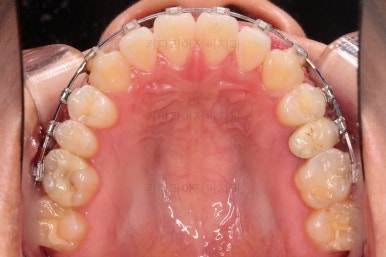

5. 치료의 종료

부산치아교정잘하는곳 키다리아저씨치과에서 치료를 종료했을 때의 사진입니다.

위아랫니가 가지런해졌고요.

다시 틀어지지 말라고 적절한 유지장치를 구성합니다.

보철 치아의 위치/크기로 인해 100% 중앙선은 맞기 힘드나 가장 잘 맞추어 놨고, 앞니의 각도도 매우 좋아졌습니다.

아래 앞니도 단순히 머리 부분만 뒤로 눕힌 것이 아니라 뿌리까지 뒤로 당겨왔고요.